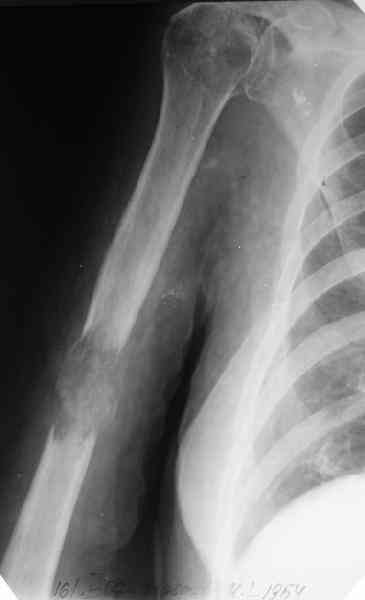

Женщина 53 лет получила патологический перелом правого плеча в феварле, и левого в марте - mts из невыясненного первичного очага.

Онкологи провели облучение, руки на косынки, время от времени наблюдают, вводили зомету.На нас вышли родственники. Состояние пациентки уже не очень, анемия (Hb -50-60 г/л), исхудалв, но асцита нет, в легких чисто. Поскольку женщина совершенно беспомощна, решили сделать остеосиннтез.

Сегодня сделали, Fixion диаметром 7,4 мм. Обе пперации продолжались по 7 мин. Картинки в приложении. Наркоз был диприваном, на спонтанном дыхании. По крайней мере, пока довольны хотя бы анестезиологи, похоже, не верили, что управимся меньше, чем за час ;-)

Гвоздик 7,4 расширяется до 11 мм. Не маловато ли, судя по снимкам?

7,4 мм, рсширяющийся до 11 мм, в принципе, достаточно для плеча. Хотя мне тоже показалось, что можно было бы и потолще. Вообще есть и следующий диаметр, 8,5 мм, расширяющийся до 13,5 мм, но его в наличии на сегодня не было.